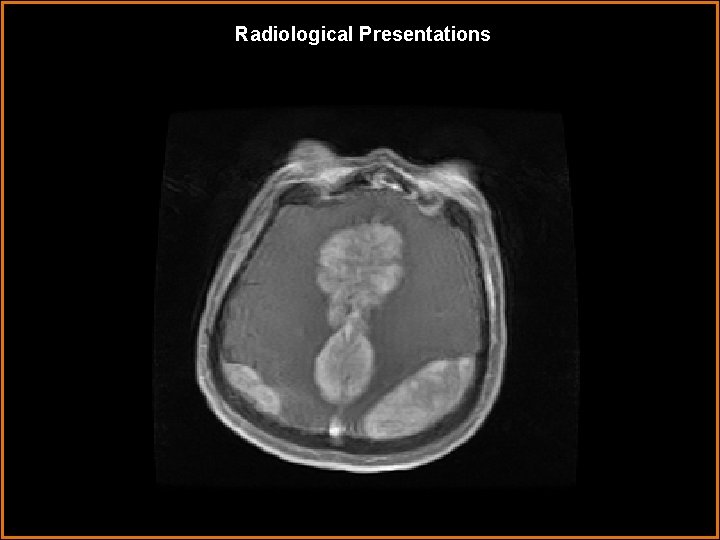

Findings and Differentials Findings: Axial T 1 -Post contrast MRI shows multiple avidly enhancing

Findings and Differentials Findings: Axial T 1 -Post contrast MRI shows multiple avidly enhancing extra-axial dural based masses. Differentials: • Multiple meningiomas • Dural metastases • Erdheim-Chester Disease